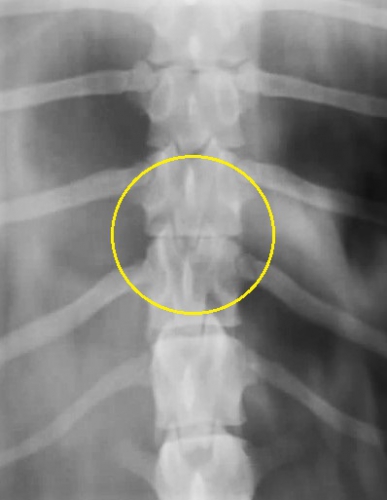

椎間板ヘルニアの確定診断や外科治療を検討する際にかかせない検査がMRIやCTです。これらの画像検査により、椎間板ヘルニアの診断と、その部位、脱出物の評価や脊髄神経にどのぐらいの障害を及ぼしているのかを正確に確認することができます。この検査によって正確な診断と適切な手術計画を立てることができます。

下の写真はのMRIでの椎間板ヘルニアの見え方の一例です。黄色丸の中にヘルニアを起こしている圧迫物質が「黒い影」として映っています。前後を走る白い棒状の脊髄神経を右下から重度に圧迫して、まるで押しつぶしているような画像が見られます。左写真がサジタル像(側面像)、右写真がコロナル像(水平の縦切り像)です。

実は、上のMRIの画像は上に示したレントゲン写真と同じ患者さんの全く同じ部位を撮影したものです。どうでしょうか?MRIの特長がなんとなくお分かりになりましたでしょうか。。。

MRIではさらに、ヘルニアを起こしている部位の特定だけではなく、周囲の脊髄神経の出血や炎症の存在、腫瘍や脊髄梗塞など、椎間板ヘルニア以外の病気の可能性を除外します。特にMRIは神経を画像で評価する能力に優れており、炎症による障害の程度や椎間板ヘルニアに伴う致命的な脊髄軟化症の診断をすることができます。